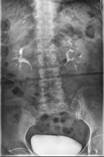

术前腰椎动力位片